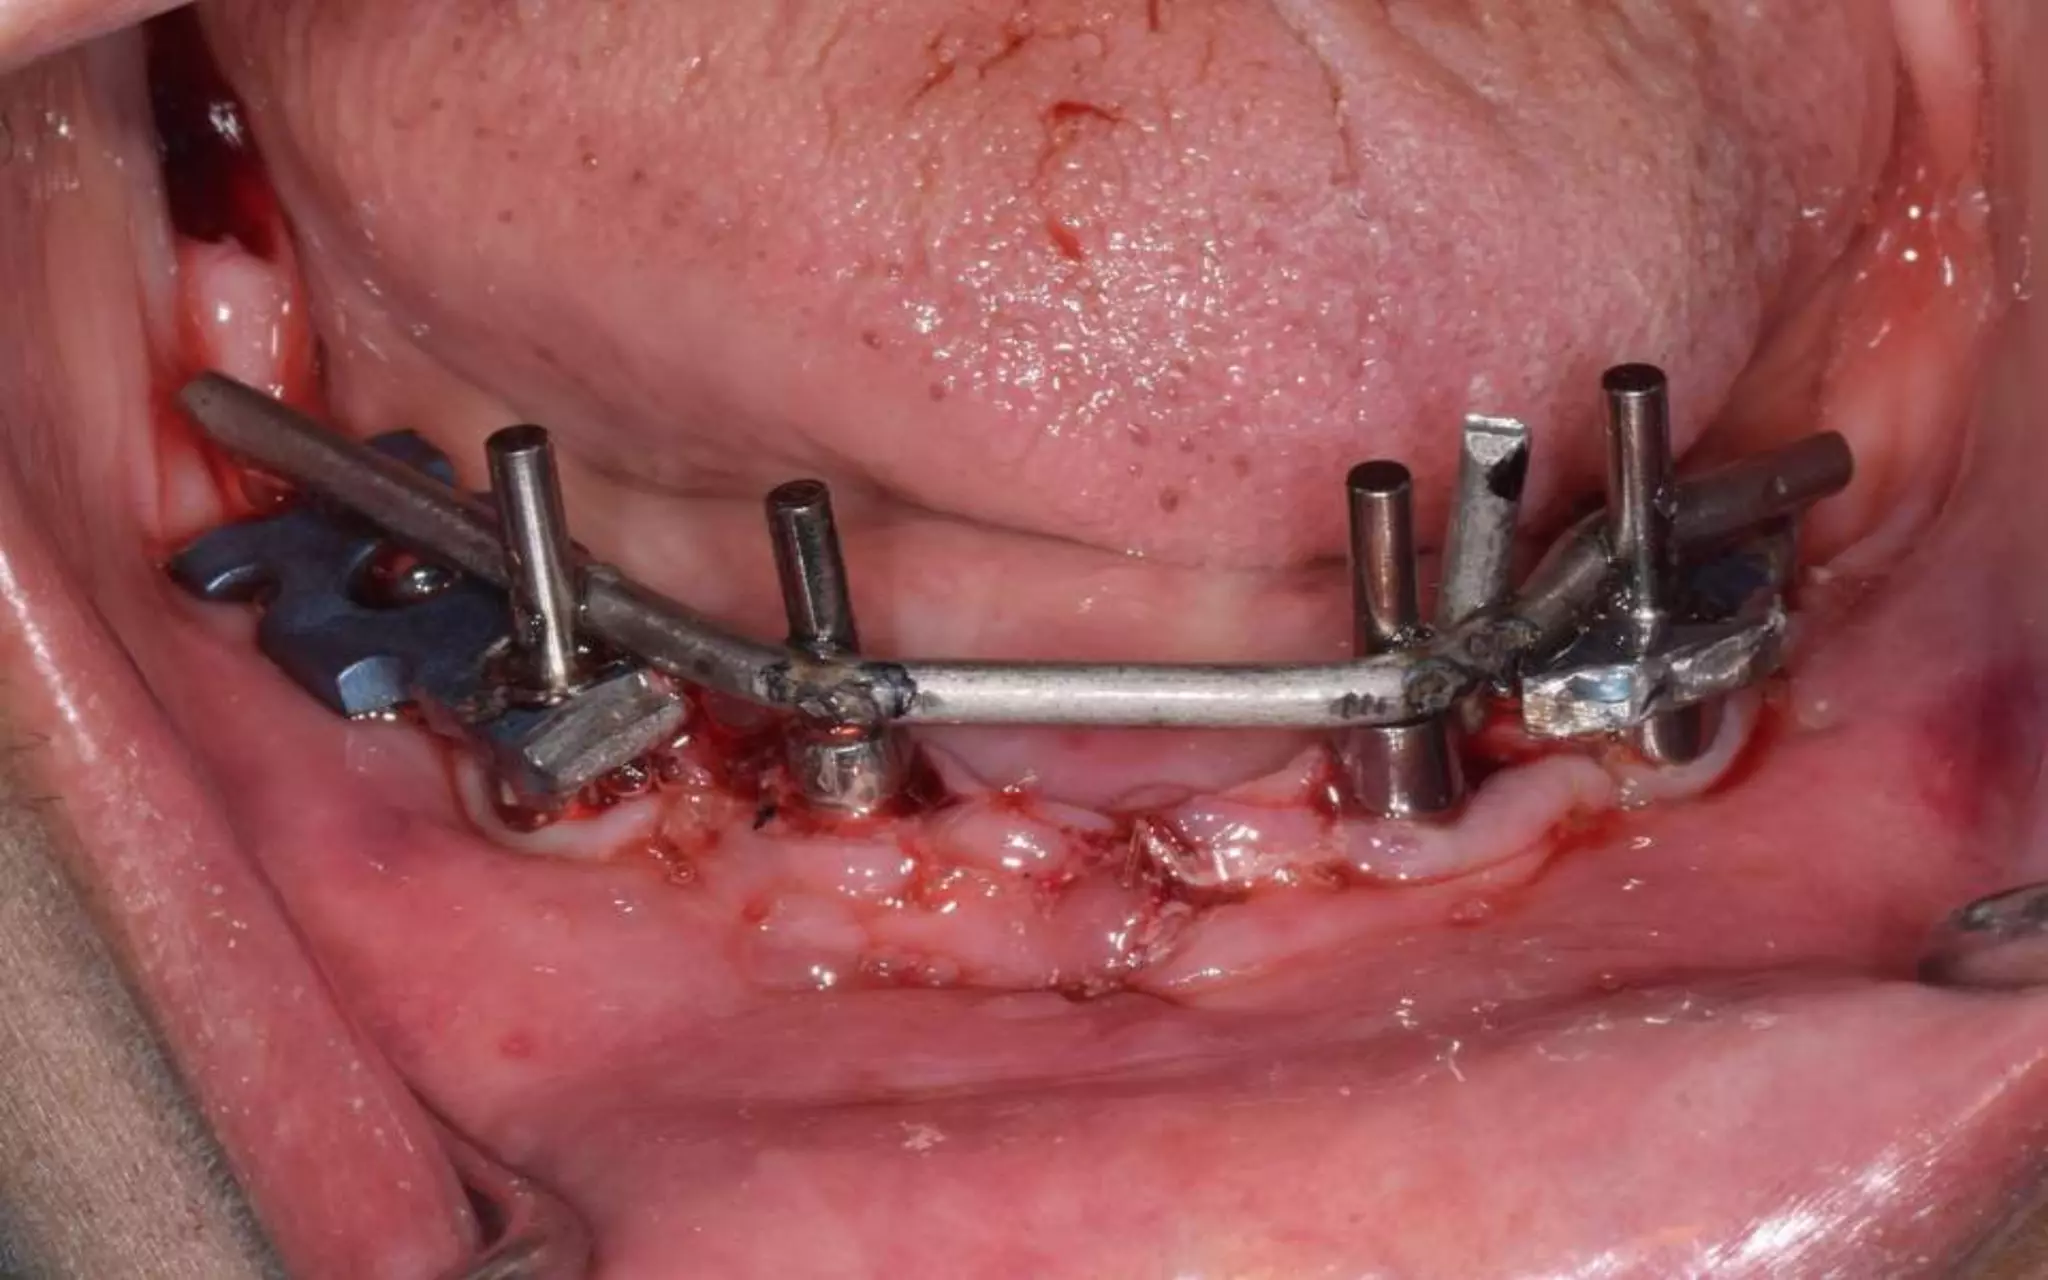

Intraoral welding

Crestal incision with releasing incisions